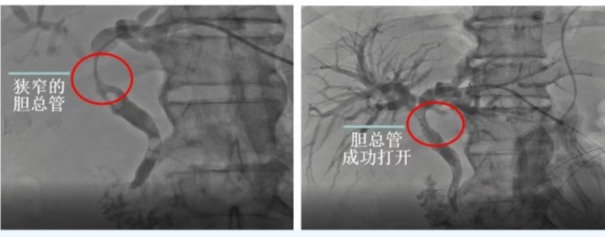

【医路速览·新闻】第165期:告别“小黄人”!超声“导航”显神通——我院消化内科团队运用胆道支架植入...

2025-07-18